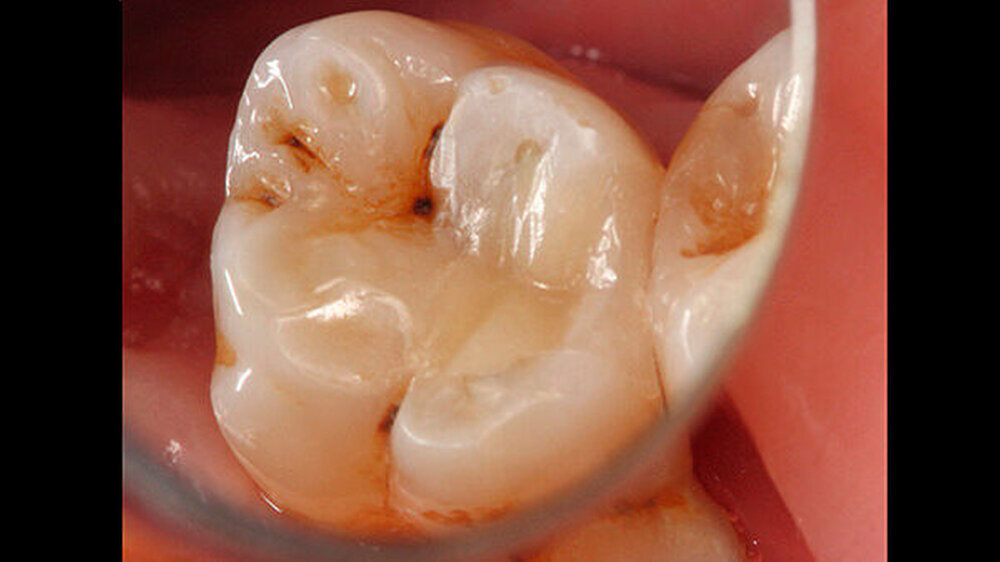

Das Zementmaterial wurde nach Herstellerangaben angemischt und mittels eines kleinen Kugelstopfers (Dycal-Instrument) im Bereich der distalen pulpalen Wand appliziert und mit einem Heidemann-Spatel adaptiert. Das Material wurde damit gleichzeitig sowohl zur Caries-profunda-Behandlung als auch zur Unterfüllung eingesetzt. Nach einer Abbindezeit für das Material von zwölf Minuten wurde der Defekt mit einer Kompositfüllung restauriert (Abbildung 4).

Zur Füllungstherapie wurde ein Etch&Rinse-Adhäsiv (ExciTE, Ivoclar Vivadent) in Kombination mit einem Feinpartikelhybridkomposit (Tetric EvoCeram, Ivoclar Vivadent) verwendet. Nach Anätzen des Schmelzes mit Phosphorsäure (Total Etch, Ivoclar Vivadent) (Abbildung 5) und Applikation des Adhäsivs (ExciTE DC, Ivoclar Vivadent) (Abbildung 6) wurde zunächst eine erste Schicht aus einem opaken, fließfähigen Komposit in die Kavität eingebracht (Venus Flow Baseliner, Heraeus Kulzer).

Das Kavitätenlining mit einem Flowkomposit ermöglicht eine gute Primäradaptation und stabilisiert den Haftverbund zum Dentin beim Einsetzen der Polymerisationsschrumpfung des nachfolgend platzierten Komposits [Haller B, 2009]. Zudem ermöglicht der opake Liner eine Abgrenzung des Übergangs zur natürlichen Zahnhartsubstanz (Abbildung 7).

Anschließend erfolgte der Aufbau der Restauration in Inkrement-Technik. Nachdem der Kofferdam entfernt wurde, wurden Okklusion und Artikulation überprüft, und es erfolgten Ausarbeitung und Politur (Abbildung 8) mit Feinkorndiamanten.